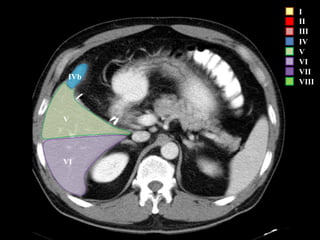

COUINAUD asignó un sistema de numeración para definir la segmentación

hepática.

I – Entre cava y porta

II – el más superior de los izquierdos

III – Por debajo del II

IV – por delante de la vesícula

V – por detrás de la vesícula

VI – relación con riñón derecho

VII – el más posterior de los segmentos superiores

VIII – domo hepático

Las claves de la segm. Hepática